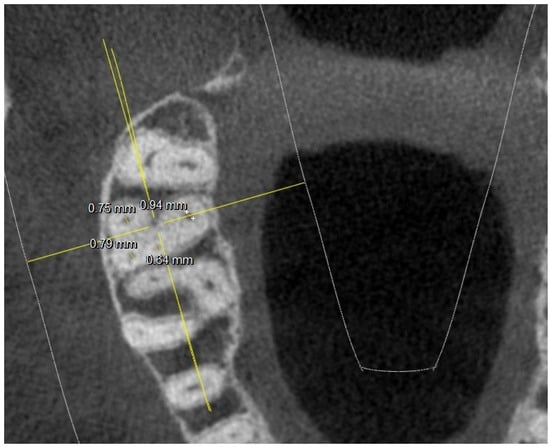

- diameter of root canal orifices;

- distance between intra- and inter-root canals;

| 3 mm from the apex: MB diameter | 0.54 | 0.22 | 0.69 | 0.18 | 0.66 | 0.12 | 0.55 | 0.11 | ||

| DB diameter | 0.54 | 0.21 (2 NO) | 0.54 | 0.17 (1 NO) | 0.58 | 0.18 (1 NO) | 0.53 | 0.16 (3 NO) | ||

| Palatal diameter | 0.87 | 0.12 | 0.86 | 0.12 | 0.82 | 0.16 | 0.59 | 0.17 | ||

| MB2 diameter | 0.39 | 0.08 (8 NO) | 0.28 | 0.06 (9 NO) | 0.44 | 0.12 (5 NO) | 0.19 | 0.07 (7 NO) | ||

| 3 mm from the apex: MB-DB distance | 4.93 | 1.89 | 2.82 | 0.67 | 4.07 | 1.76 | 3.06 | 1.99 | ||

| DB-P distance | 8.6 | 2 | 7.12 | 1.9 | 8.12 | 2.6 | 6.64 | 1.89 | ||

| P-MB2 distance | 8.48 | 2.42 | 5.7 | 1.88 | 7.6 | 2.43 (12 NO) | 5.55 | 1.68 | ||

| MB1-MB2 distance | 1.48 | 0.41 | 0.87 | 0.22 | 1.72 | 0.41 | 1.76 | 0.45 | ||

| MB-P distance | 9.13 | 2.12 | 7.23 | 1.99 | 8.85 | 2.43 | 6.48 | 1.88 | ||